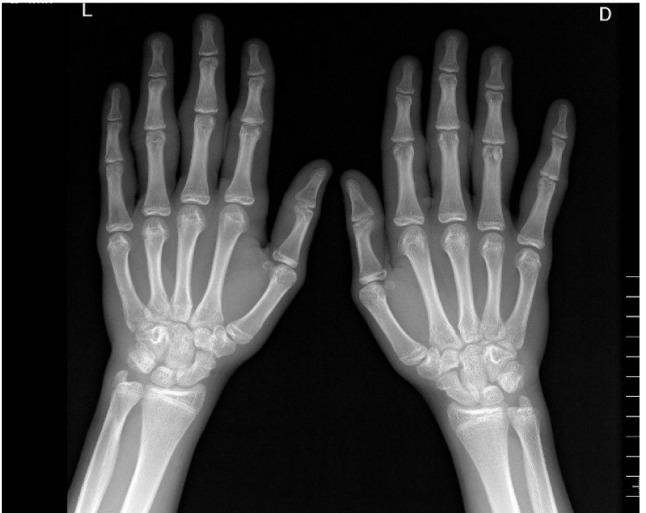

厚皮性是一种罕见的不明原因的数字纤维瘤病,主要影响青少年男孩。它表现为对称,无痛的软组织增厚,通常在近端指间关节(PIP)周围。患者经常经历延迟诊断,接受不必要的治疗,或被误诊为慢性炎症性关节炎。虽然确切原因尚不清楚,但厚皮畸形可能与重复性机械创伤有关,如手指摩擦或交叉,可导致继发性皮肤增厚。由于其预后良好,通常不需要治疗,尽管一些患者由于这种情况对美容的影响而要求治疗。本研究的目的是介绍在萨格勒布儿科风湿病门诊诊断为厚皮性的7例患者的特征。此外,我们使用PubMed和谷歌Scholar对1975年至2024年发表的报告病例进行了全面的文献综述。观察到的主要症状是PIP和掌指关节周围软组织肿胀,一些患者出现类似指关节垫的角化斑。一名患者经历了手部疼痛。进行临床检查和诊断检查(针对风湿病的实验室检查,放射学检查,如关节超声、x射线或磁共振成像,或皮肤活检),以排除具有类似临床特征和病因的其他疾病,如青少年特发性关节炎。根据国际风湿病协会联盟的分类标准,所有患者均不符合青少年特发性关节炎的标准。提高对厚皮病的认识和实现准确诊断可以减少不必要的诊断测试、治疗和患者焦虑。

Pachydermodactily is a rare digital fibromatosis of unknown origin, mainly affecting adolescent boys. It presents as symmetrical, painless thickening of the soft tissues, usually around the proximal interphalangeal joints (PIP). Patients often experience delayed diagnoses, receive unnecessary treatments, or are misdiagnosed with chronic inflammatory arthritis. Although the exact cause remains unclear, pachydermodactyly may be associated with repetitive mechanical trauma, such as rubbing or interlacing the fingers, which can lead to secondary skin thickening. Treatment is often not required given its benign prognosis, although some patients ask for therapy due to the cosmetic impact of the condition. The aim of this study was to present the characteristics of seven patients diagnosed with pachydermodactily at pediatric rheumatology outpatient clinics in Zagreb. Additionally, we performed a comprehensive literature review of reported cases published from 1975 to 2024 using PubMed and Google Scholar. The primary symptom observed was swelling of the soft tissues around the PIP and metacarpophalangeal joints, with some patients presenting with hyperkeratotic plaques resembling knuckle pads. One patient experienced hand pain. Clinical examination and diagnostic workup were performed (laboratory tests specific for rheumatologic diseases, radiological tests such as joint ultrasound, x-ray or magnetic resonance imaging, or skin biopsy) to exclude other conditions with similar clinical features and etiologies, such as juvenile idiopathic arthritis. None of the patients met the criteria for juvenile idiopathic arthritis according to the classification criteria of the International League of Associations for Rheumatology. Increasing awareness of pachydermodactyly and achieving accurate diagnoses can reduce unnecessary diagnostic tests, treatments, and patient anxiety.